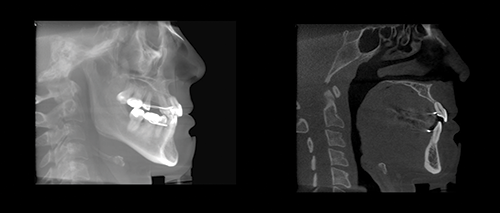

From a cephalometric perspective, the damage is difficult to visualize. Alveolar bone dehiscence and fenestration is impossible to accurately diagnose with cephalograms because of the wide focal width causing superimposition of structures. However, cone-beam computed tomography (CBCT) can quantify the damage on a slice-by-slice basis (Fig. 6). In this case, a 2019 CBCT scan revealed extreme alveolar bone loss (Fig. 7).

Ignoring Biological Limitations

Fig. 7: End-stage AGGA CBCT-generated lateral cephalogram compared to a sagittal slice of an upper central incisor from the same CBCT scan. The sagittal CBCT slice depicts extreme alveolar bone loss from adaptive resorption, resulting in minimal incisor bone support. Patient-provided scans.

Unfortunately, rather than using proper CBCT techniques to evaluate the alveolar bone and root conditions, the CBCT scans were often used only to generate conventional 2D lateral cephalograms, forfeiting the diagnostic advantage of three-dimensional imaging. This two-dimensional view masks the extent of damage. It is worth considering whether, if the patient’s provider had accurately utilized the CBCT scans throughout treatment to assess individual slices, the treatment could have been stopped or altered to reduce the extent of damage.